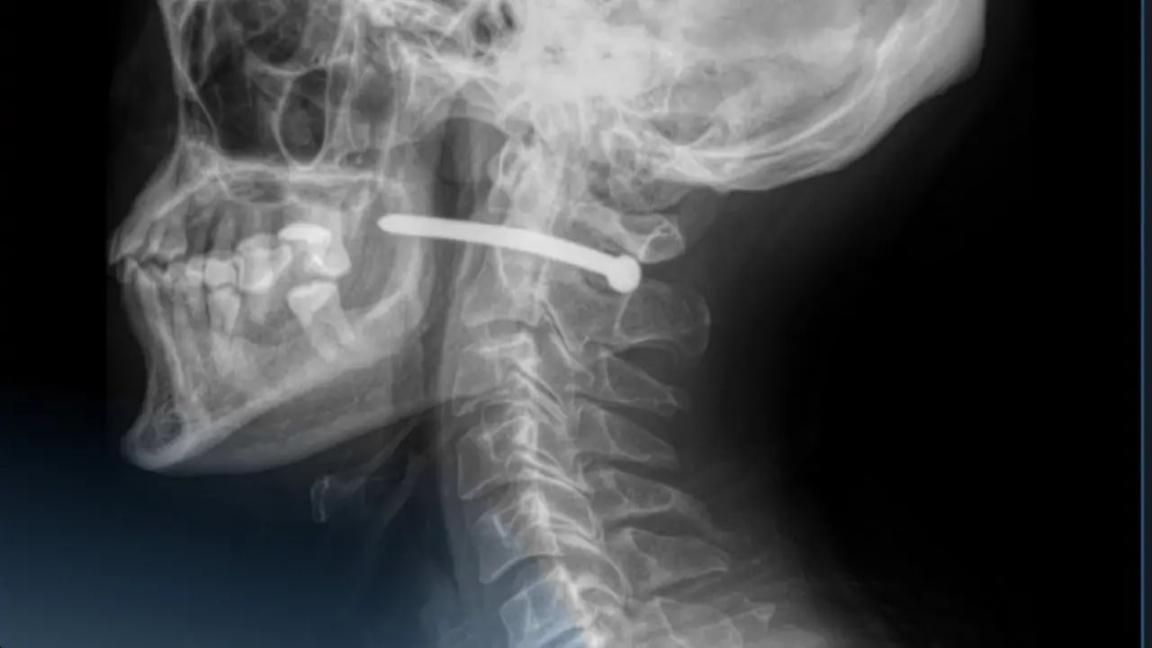

پەتروپاۆلدا كوپسالالى قالالىق جەدەل جاردەم اۋرۋحاناسىنىڭ حيرۋرگتارى 51 جاستاعى ەر ادامنىڭ موينىنداعى شەگەنى ءساتتى الىپ تاستادى، دەپ حابارلايدى Dalanews.kz.

بەلگىلى بولعانداي، وقىس جاعداي ەر ادام ۇيىندە جوندەۋ جۇمىستارىن جۇرگىزىپ جاتقان كەزدە بولعان. ابايسىزدا پنيەۆماتيكالىق تاپانشادان اتىلعان شەگە ونىڭ موينىنا كىرىپ كەتكەن.

دارىگەرلەر بوگدە زاتتى ءساتتى الىپ، جارانى تازالاپ، وڭدەگەن.

ابىروي بولعاندا، مويىن ايماعىنداعى ومىرگە ماڭىزدى تامىرلار مەن جۇيكەلەر زاقىمدانباعان.